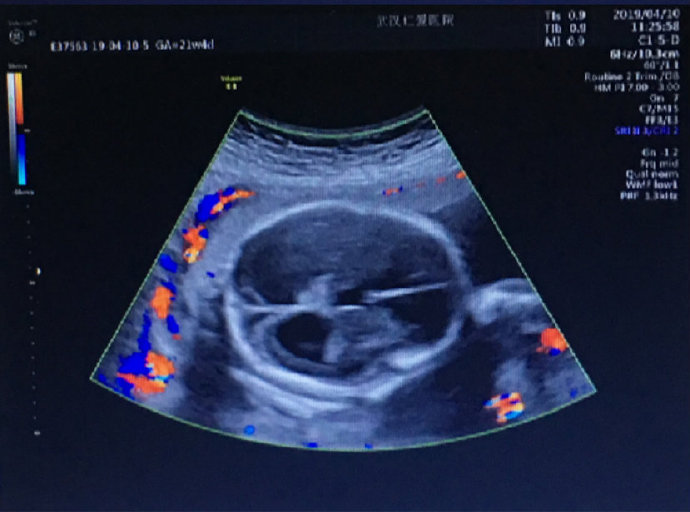

這位孕媽姓劉,家住漢陽,今年24歲,孕22周。前幾日在武漢仁愛醫(yī)院做產(chǎn)檢時(shí),被醫(yī)生告知胎兒重度腦積水。聽到這個(gè)震驚的消息,劉女士?jī)?nèi)心難受不已。

武漢仁愛醫(yī)院超聲影像科王娟主任介紹:“很多初次懷孕,尤其是意外懷孕的女性因?yàn)闆]有懷孕經(jīng)驗(yàn),甚至不會(huì)往懷孕方面去想。當(dāng)她們因?yàn)閼言卸霈F(xiàn)頭痛、體溫升高、犯困、身體乏力、食欲不振等早孕癥狀時(shí)常常會(huì)誤認(rèn)為自己生病了而誤服藥物,這些藥物對(duì)胎兒的傷害是特別大的,尤其是在懷孕3個(gè)月之內(nèi),這個(gè)時(shí)期是胎兒發(fā)育最活躍的時(shí)期,必須在醫(yī)生引導(dǎo)下謹(jǐn)慎用藥。”